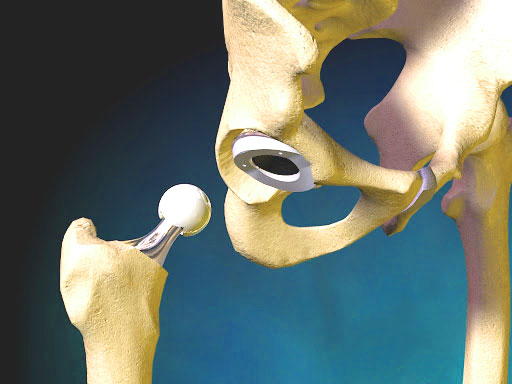

Le Centre international de chirurgie orthopédique de Barcelone (B.I.C.O.S) s'engage à fournir un traitement de haute qualité aux adultes souffrant de troubles orthopédiques. Son objectif est de fournir des soins médicaux approfondis et fondés sur des preuves aux patients dans leur langue maternelle par un groupe d'experts hautement qualifiés dans le domaine de la chirurgie reconstructive pour adultes basé à Barcelone, en Espagne. Nous croyons en une approche éthique de la médecine basée sur la solidarité avec les besoins et les circonstances de nos patients. Les voyages internationaux et les traitements médicaux sont des problèmes complexes, mais nous essayons de répondre aux besoins et exigences personnalisés de chaque patient, tout en maintenant notre niveau de soins.

Le groupe se compose de certains des chirurgiens les plus expérimentés et les mieux formés du pays, ayant effectué des milliers d'interventions orthopédiques allant du remplacement articulaire, des fusions vertébrales aux reconstructions arthroscopiques. Ils comprennent des chirurgiens formés par une bourse aux États-Unis et au Royaume-Uni dans le domaine de la chirurgie de la colonne vertébrale, de la chirurgie reconstructrice des adultes par arthroscopie et du remplacement articulaire. Nous sommes des chirurgiens expérimentés avec des parcours diversifiés et une formation internationale et pouvons donc comprendre les nuances que recherchent des personnes de cultures différentes dans une relation médecin-patient.

L'un des principes de la pratique médicale de BICOS (et un reflet des croyances personnelles de ses membres) est celui de la transparence, de l'honnêteté et de la gestion éthique du secteur médical. Un effort a été consciencieusement fait pour ne pas avoir de liens conflictuels avec l'industrie médicale ou les sociétés d'implants. Nous n'avons aucune divulgation ou conflit d'intérêts dans notre pratique. Les implants indiqués et les principes appliqués dans notre pratique sont uniquement basés sur la survie des implants à partir de revues évaluées par des pairs et de données de registre.

Notre idéal est de fournir une solution honnête et directe à différents problèmes orthopédiques grâce à une médecine factuelle de haute qualité avec une réelle préoccupation pour chaque patient. Nous croyons qu'il est important de répondre aux préoccupations de chaque patient après avoir fourni un diagnostic clair avec un plan à court, moyen et long terme en fonction de leur maladie ou de leur blessure. Il est important pour nous que le patient comprenne et s'implique dans la résolution de ses problèmes musculo-squelettiques. Nous croyons que nos patients sont nos partenaires et nous voulons leur donner des connaissances et une éducation sur leur pathologie tout en utilisant les techniques et les options de traitement les plus à jour disponibles. La solidarité et l'éthique sont des valeurs importantes pour nous du fait de notre travail continu dans la fourniture de soins de santé dans les régions défavorisées où nous avons poursuivi des programmes cliniques et de formation. Nous nous efforçons de fournir une solution aux patients dans des circonstances difficiles car nous pensons que les soins de santé sont un droit et une nécessité. Nous considérons la pratique de la médecine comme une vocation et un privilège et non comme une entreprise. Notre pratique est basée dans deux cliniques externes distinctes (centres médicaux Clinica Teknon et Catalonia), mais toutes les chirurgies sont effectuées à la Clinica Teknon agréée par la Commission mixte internationale.